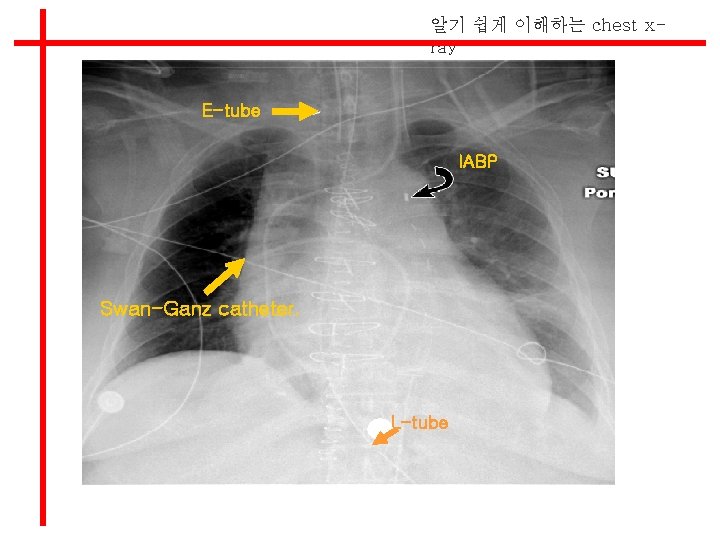

알기 쉽게 이해하는 chest xray l Position of Tubes and Catheters

알기 쉽게 이해하는 chest xray Swan Ganz catheter l 근위부 폐동맥 내 위치 l Mediastinal shadow 2 cm이내에 위치

알기 쉽게 이해하는 chest xray E-tube IABP Swan-Ganz catheter. L-tube